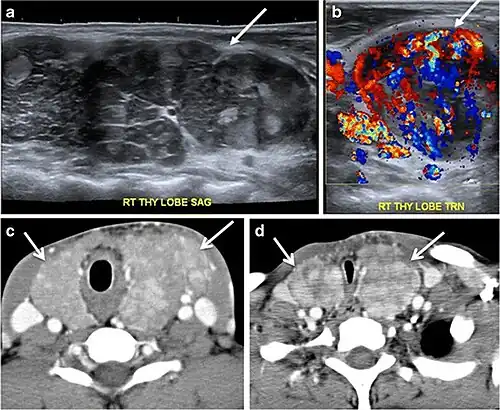

Fig. 14. A 19-year-old male patient known to have multi-nodular goiter and FNA, showing underlying Hashimoto's thyroiditis. a, b Sagittal and transverse greyscale and colour Doppler ultrasound of the neck demonstrate a hypoechoic enlarged right thyroid lobe with small hyperechoic regenerative nodules and marked hypervascularity (white arrows). c, d Enhanced axial CT scan images of the neck demonstrate a heterogeneously enhancing and enlarged thyroid gland, left more than right lobe, and the trachea is markedly narrowed.[1] -

Fig. 15. A 33-year-old female patient who presented with neck swelling and pain and was later diagnosed with Hashimoto's thyroiditis. an Axial enhanced CT scan of the neck demonstrates minimal diffuse enlargement of the thyroid gland, especially the isthmus (white arrow). b Transverse greyscale ultrasound of the neck demonstrates heterogeneously enlarged thyroid and thickened isthmus, measuring 8.6 mm.[1]

Malignancy can coexist within the goiter and a CT scan may give a clue if there are abnormal cervical lymph nodes and/or signs of invasion. Retrosternal extension (Fig. 15) could affect the surgical approach, as a lower extent may require a partial or total sternotomy to facilitate complete resection. Therefore, the distance of the retrosternal extent from the sternal notch should be measured on a sagittal image.[1]

The interpreting radiologist should describe the mass effect, detailing its degree and direction of displacement of central structures, including the trachea, oesophagus, larynx, and pharynx. Attention should be directed to the upper extent of the goiter and structures immediately surrounding the thyroid gland, including the neuro-vascular structures, retropharyngeal space, and pre-vertebral space. The reporting radiologist should evaluate the vocal cords for symmetry and signs of vocal cord palsy.[1]